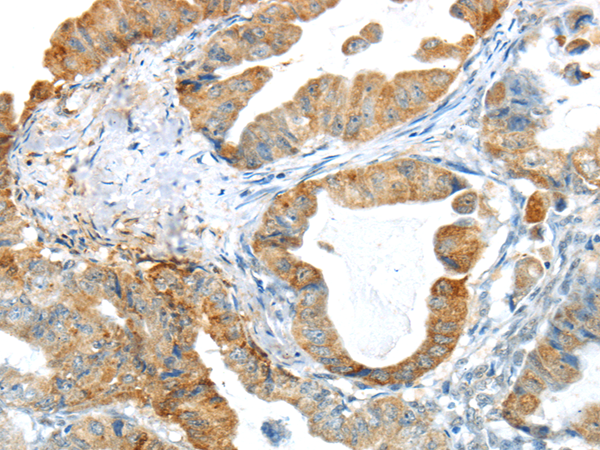

分类: 科研抗体货号: P04437别名: 42A, 18A2, CAPL, FSP1, MTS1, P9KA, PEL98应用: IHC反应种属: Human